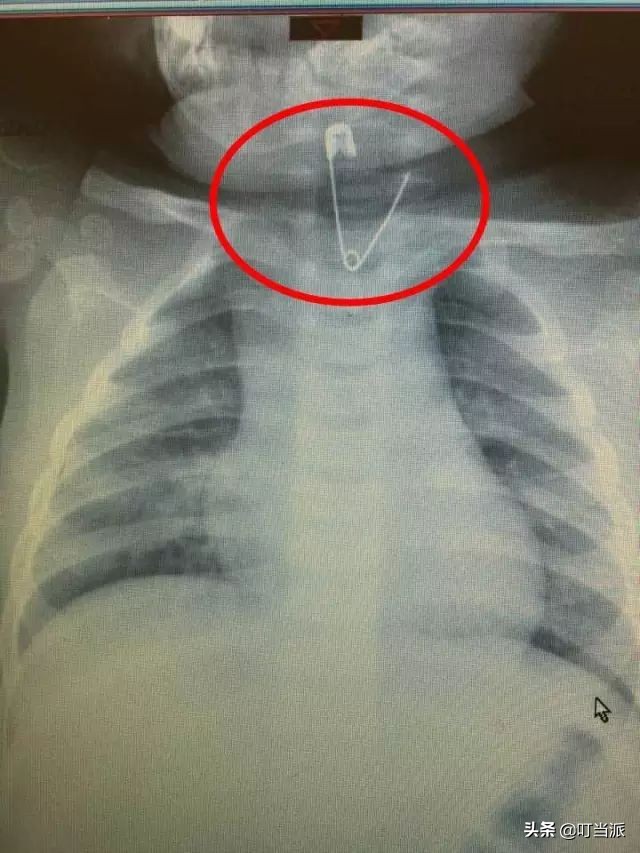

天呀!竟然还有孩子吃下了别针这种东西:

图片来源:漯河交通广播